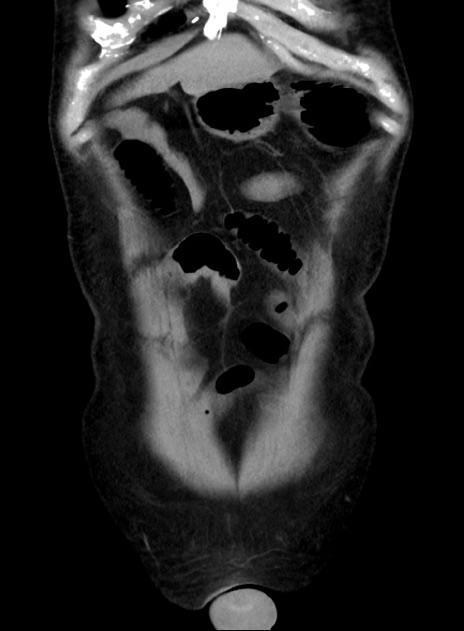

症例38(冠状断像)

【症例】70歳代 男性

【主訴】腹痛・嘔吐

【現病歴】昨晩より、嘔吐・腹痛あり。今朝になっても嘔吐あり。来院。

【既往歴】心臓バイパス手術、開腹胆摘、腸閉塞

【身体所見】BP 107/71mmHg、HR 116/min、腹部:平坦、軟、下腹部に軽度圧痛あり。反跳痛なし。

【データ】WBC 15100、CRP 0.32